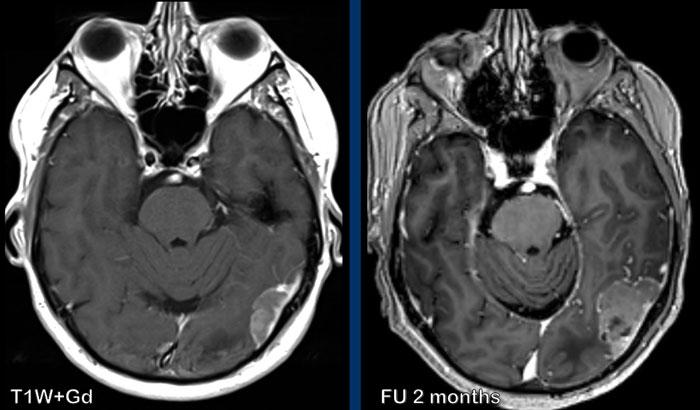

Các hình ảnh này của một nam giới 58 tuổi mắc ung thư phổi.

Có hai tổn thương bắt chước hình ảnh của u màng não.

Tiếp tục xem các hình ảnh theo dõi…

Trên hình ảnh theo dõi sau 2 tháng, tổn thương phát triển đáng kể.

Hiện tại bờ tổn thương không đều.

Đây hóa ra là di căn màng cứng.